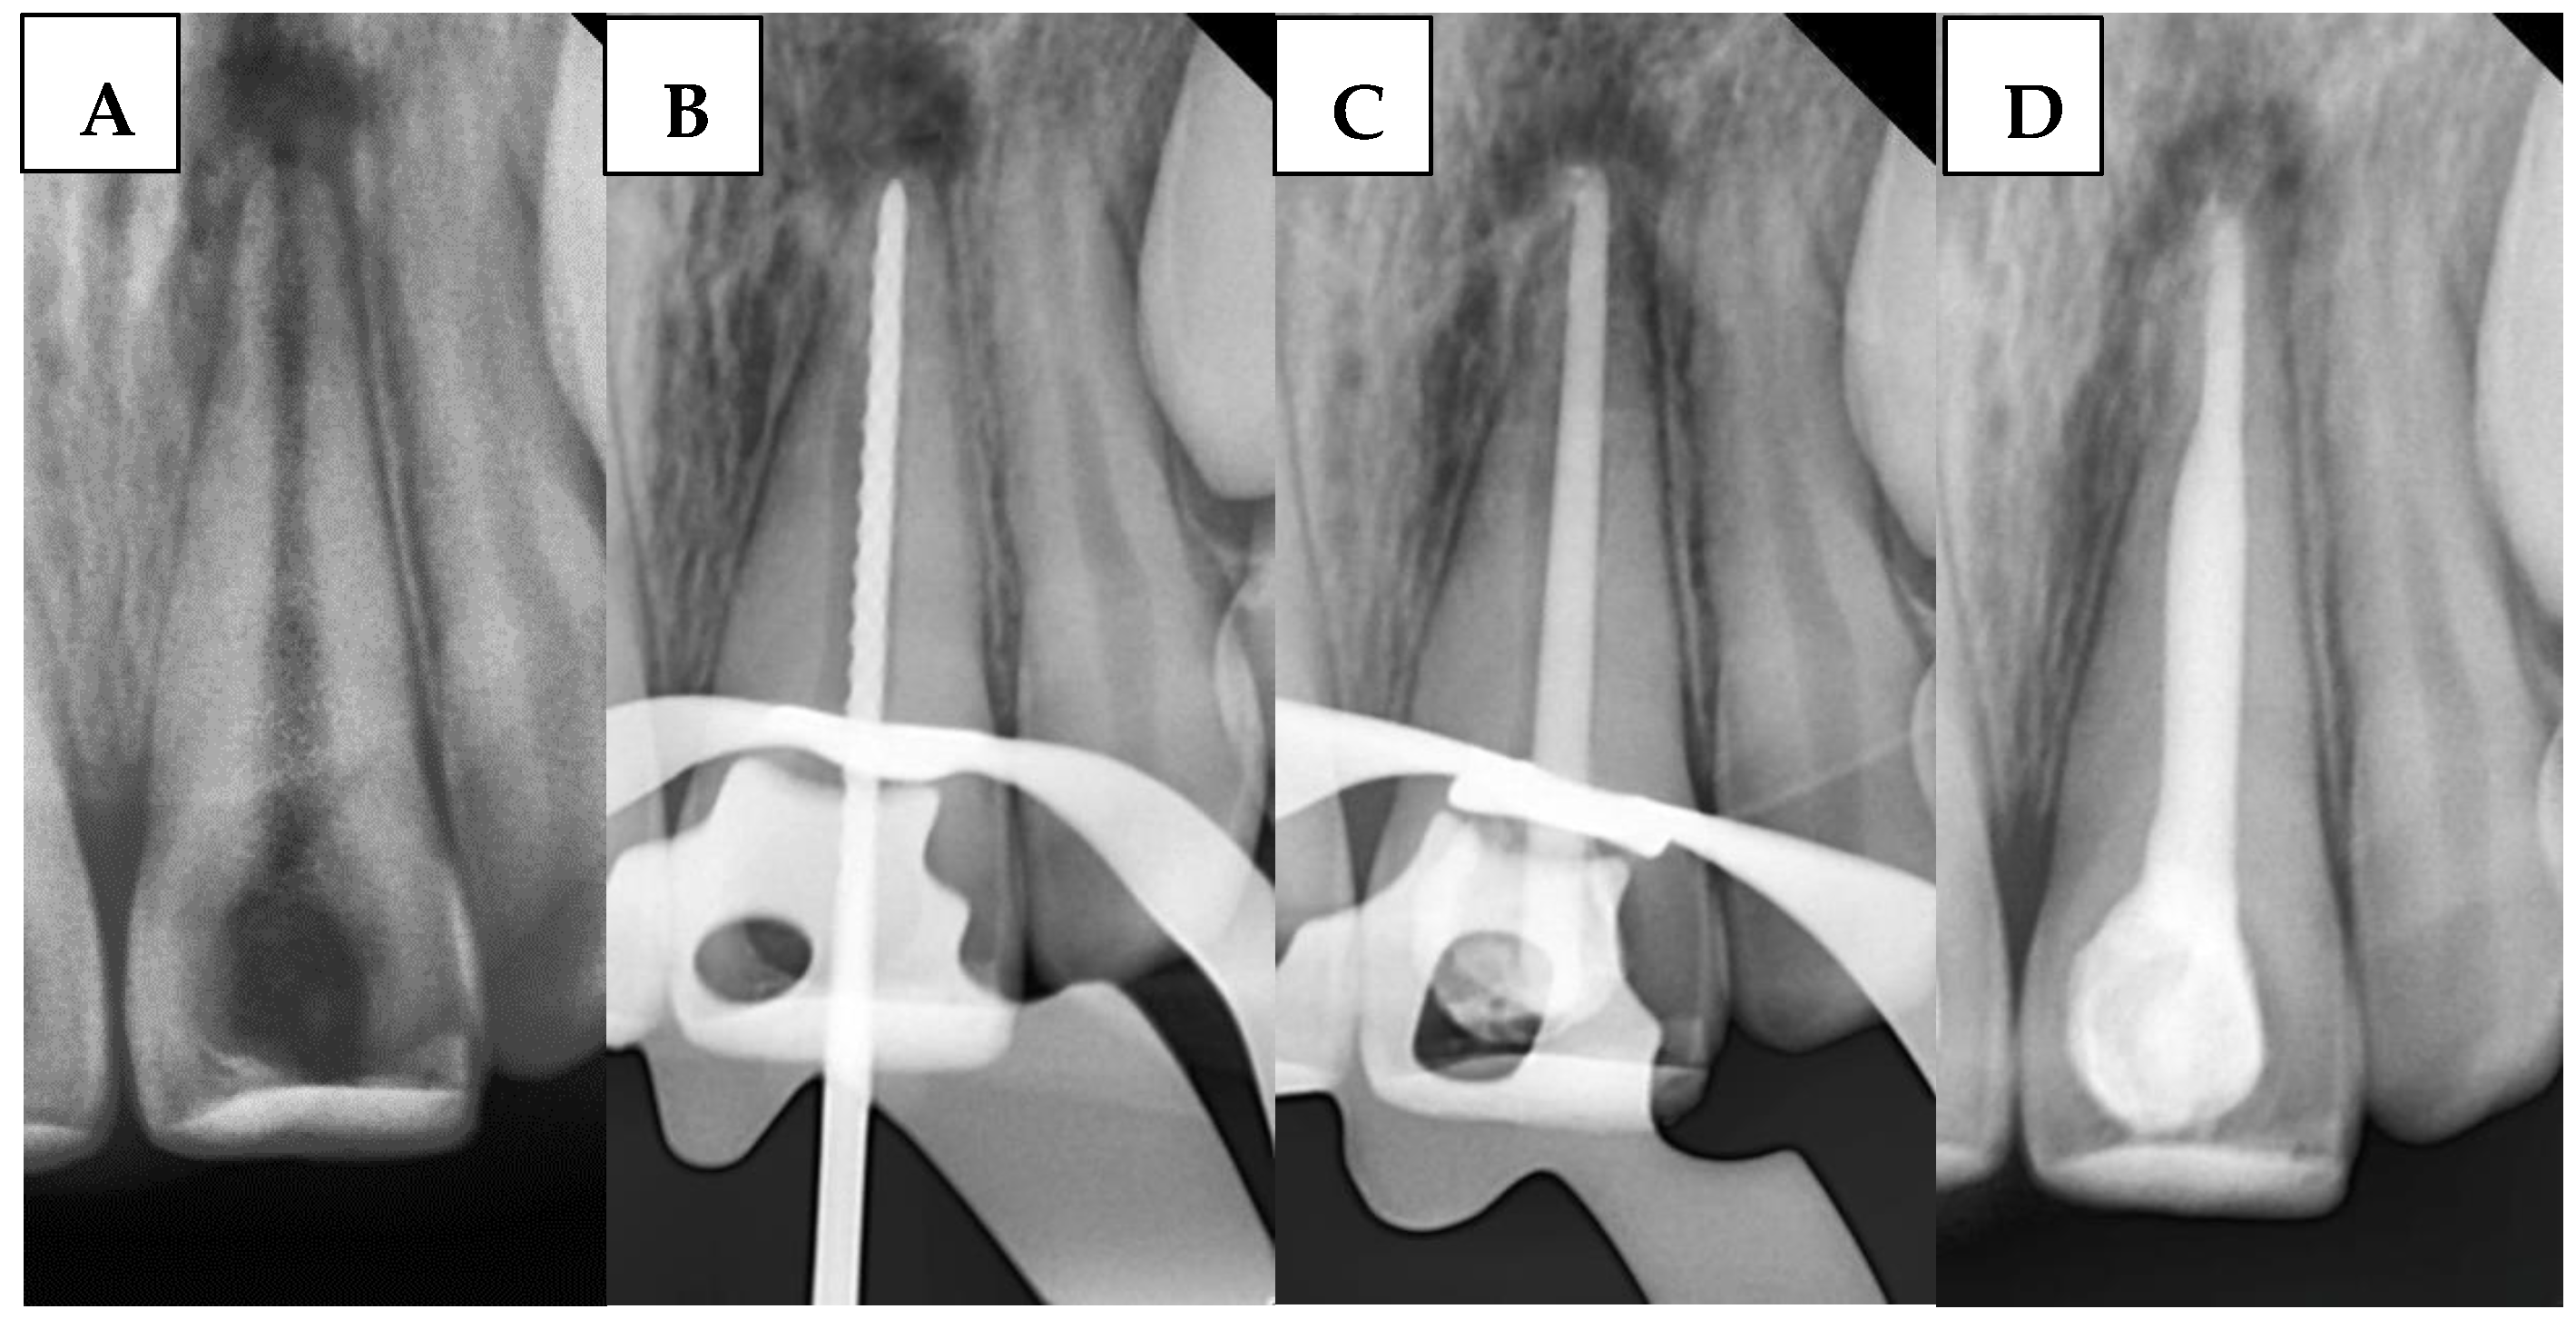

2.6.5. BioCeramic Putty and Sealer Mixture (BPSM) Group

A radiograph was first taken with the hand plugger to ensure that it reached 4 mm short of the radiographic apex, as specified by the WL. The immature canal was gently filled with BC. Then, 3 to 5 small pellets (1 mm diameter) of BP were inserted into the canal orifice using a modified cannula [34] and gently plugged with hand pluggers. Finally, an apical radiograph was taken to confirm that the canal was properly filled with a 4 mm BioCeramic apical plug without gaps and voids. Any BioCeramic extrusion was recorded at this stage in the DPF. The incisors were then temporized with a cotton pellet and glass ionomer filling. The following day, after isolation and removal of the temporary filling and cotton pellet, the remaining canal space was obturated with gutta-percha and BS using the cold lateral condensation technique. A periapical radiograph confirmed that the canal was obturated without voids or gaps. Figure 4 illustrates the steps of the procedure in the BPSM group.

Figure 4. Sequential steps of the procedure in the BPSM group: (A) Preoperative periapical radiograph, (B) Working length radiograph, (C) Plugger fit, (D) Apical plug formation, and (E) Postoperative radiograph.